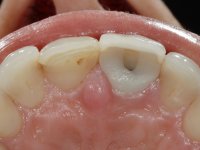

52-year-old female patient, non-smoker. He used an appointment with an implant already placed in the 1.1 site. It was provisionally rehabilitated with a composite resin crown adhered to the palatal surface of the adjacent teeth. This provisional had taken off several times in the last month, even in this first consultation it was taken off. We took advantage of this situation and verified that the “Tissue Level” implant had 2 to 3 mm of prosthetic space available. A deep bite and the inclination of the long axis of the implant posed a very difficult situation for the rehabilitator. If one chooses a abutment with a cemented crown, the height of the abutment would be minimal, with no retention or resistance. If a screwed solution is chosen, the screw access hole would emerge through the vestibular surface. It should be remembered that in 2006 the prosthetic solutions for this situation were limited to these options: 1- Screw-retained angled metal abutment for cemented crown 2 - Screw-retained angled metal abutment for transversally screw-retained crown 3 – Syn Octa metal abutment for screw-retained crown. A serious problem in this rehabilitation was guessed right from the start. The patient had a thick gingival phenotype and good oral hygiene.